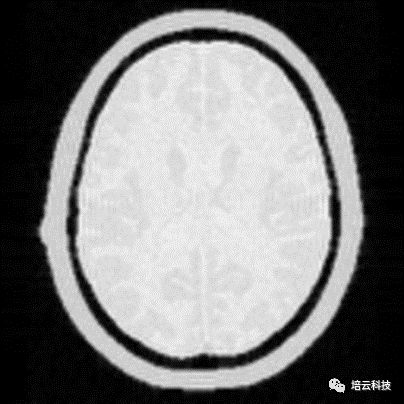

图4 TR=300ms,TE=145ms时,脂肪和水信号幅值相同,图像上等亮

同理,如果保持TR不变,增加TE=200ms,数值计算显示,脂肪和水的回波信号幅值将逆转,水的信号反而略高,对应到图像上将出现水比脂肪稍亮的效果,图5所示。当然这种参数组合在临床极少得到应用,因为对比不高,同时信噪比很差,没有价值。